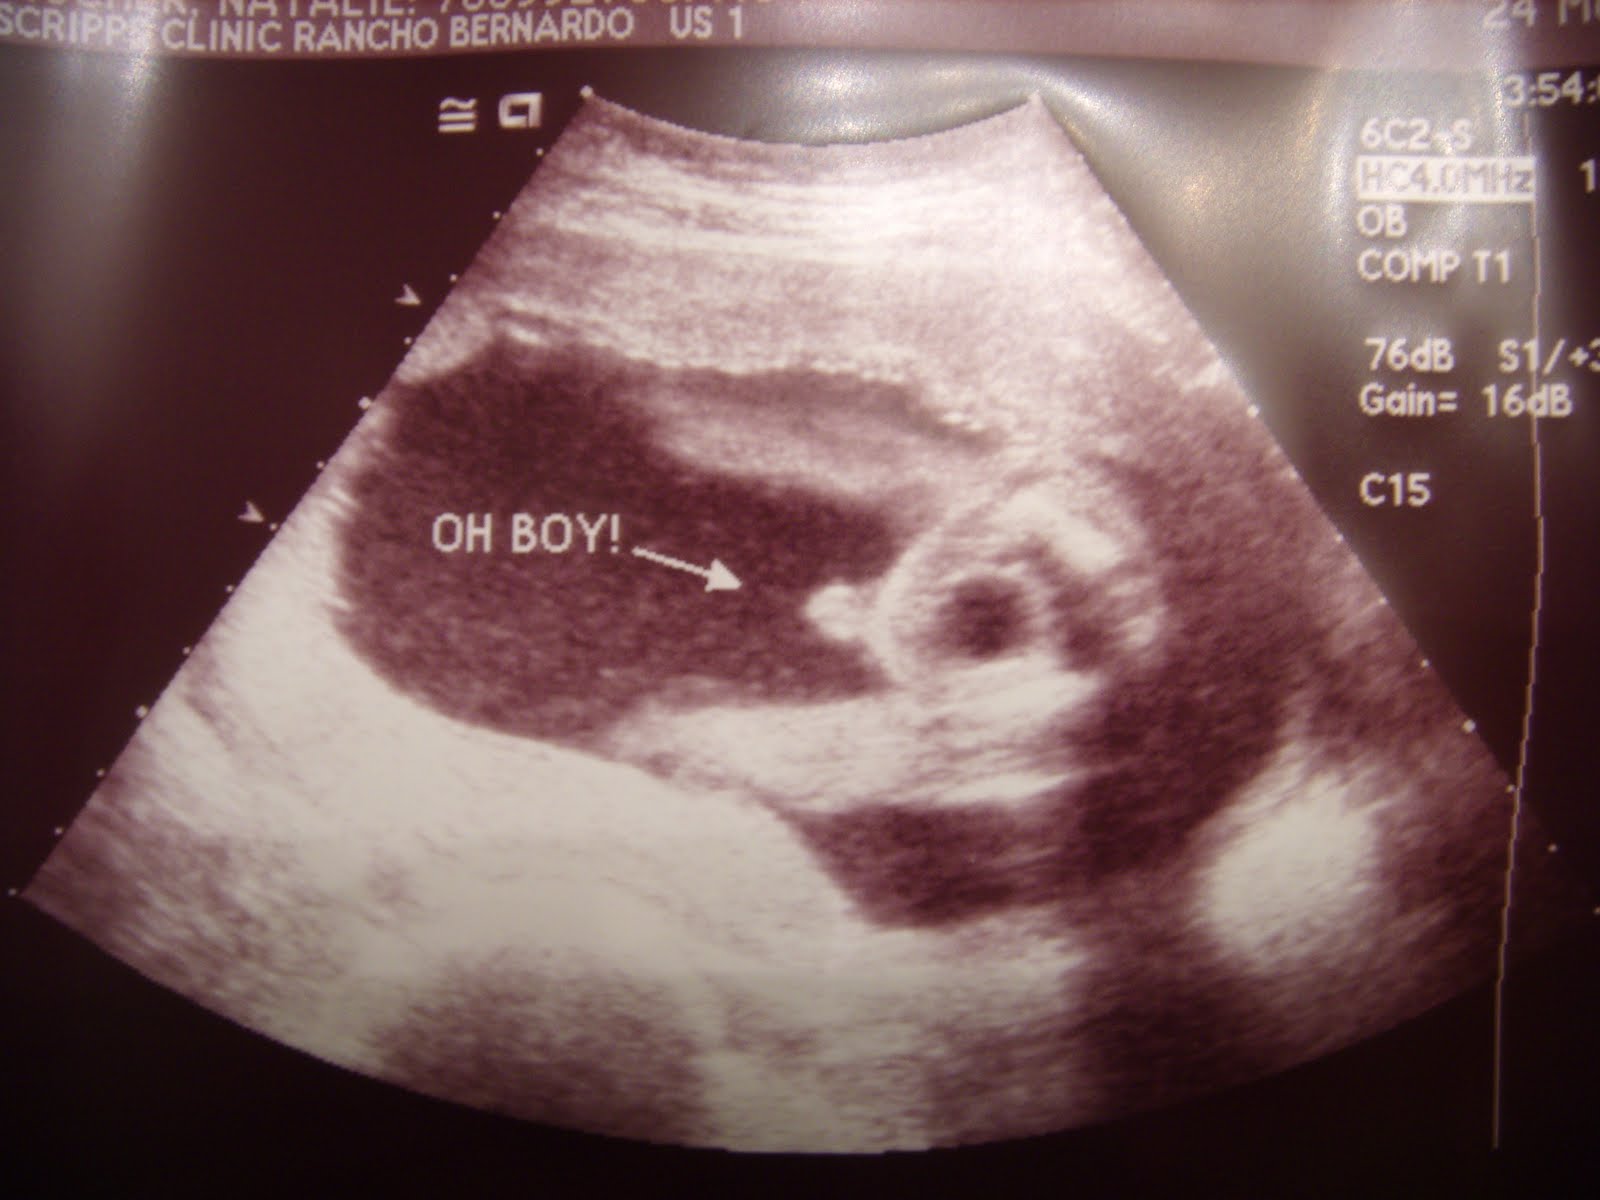

Peenie

The little black donut behind his peenie is his full bladder- he was holding it too! :)